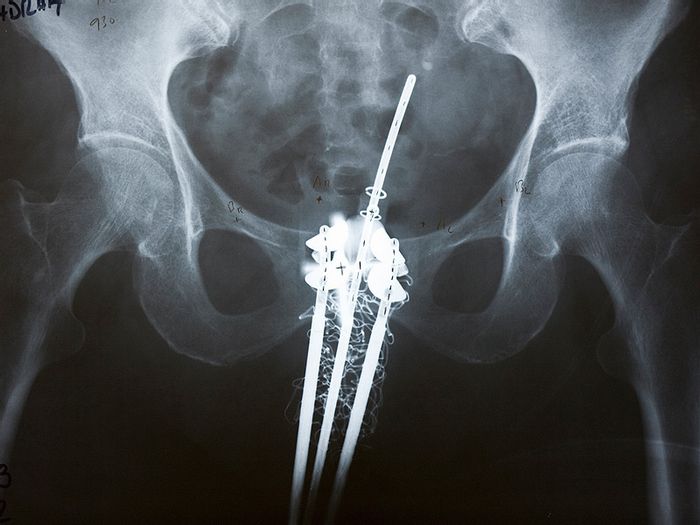

Over the course of several weeks they stop giving off radiation. Ldr prostate brachytherapy involves placing radioactive sources in the prostate permanently rather than being placed temporarily as is the case with hdr brachytherapy. Webmd describes how radioactive seed implants a form of radiation therapy called brachytherapy is used to treat prostate cancer. Find out about what your doctor might suggest if you have these side effects.

For larger implants you might have to stay in bed and lie still to keep it from moving. Your doctor will explain the risk of you getting certain side effects before you start treatment. Brachytherapy can be used to treat prostate cancer in the form of prostate seed implants during this procedure your doctor will place 80 120 small radioactive seeds into your prostate. Some people have no or very mild side effects.

Having brachytherapy with external beam radiotherapy may make some side effects more severe. The seeds or pellets are about the size of rice grains and rarely cause problems. Urinary symptoms are the most common. Yes there can be side effects or unwanted changes in your body when you have brachytherapy.